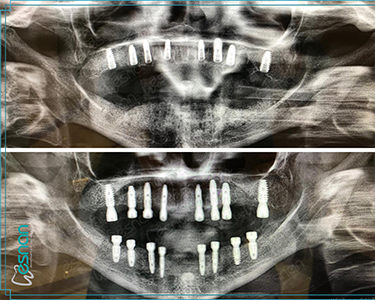

• Planning for dental implants

Our Radiology Unit in Istanbul is equipped with state-of-the-art technology to provide comprehensive dental imaging services. We offer a range of examinations, from standard panoramic X-rays to more advanced 3D imaging like CBCT scans. These tools are essential in helping our dental professionals accurately diagnose and plan treatment for various conditions, ensuring you receive the best possible care.

Each examination listed above serves a specific purpose in dental diagnostics. Panoramic X-rays provide a broad view of your teeth, jaws, and surrounding structures, while intraoral radiography offers detailed images of individual teeth. Cephalometric X-rays assess facial growth and development, and CBCT scans provide detailed 3D images for complex cases like implant planning and oral surgery. Our experienced team is dedicated to utilizing these technologies to deliver precise and personalized care for every patient.

• Dental Cone Beam Computed Tomography (CBCT)